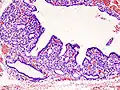

![]() | |

| Triiodothyronine (T3, pictured) and thyroxine (T4) are both forms of thyroid hormone. | |